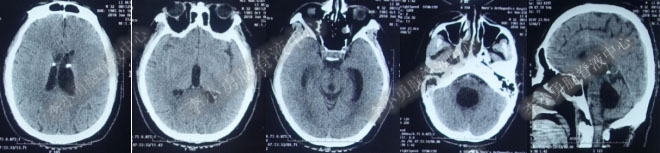

第1次内镜术后330余天即11个月(2017年4月),又开始出现头晕症状并逐渐加重。2017年6月13日(第1次内镜术后367天),行头部MRI(图-4)检查显示全脑室系统扩大。

图-4:2017年6月13日头部MRI

2017年6月19日(第1次内镜术后404天即一年零39天),因原症状加重,第2次住入该院。2017年6月20日(住院第2天),复查头部MRI(图-5)。

图-5:2017年6月20日头部MRI

2017年6月27日(分流术后5天),复查头部CT(图-6)显示幕上脑室及第四脑室均有所缩小。

图-6:2017年6月27日头部CT